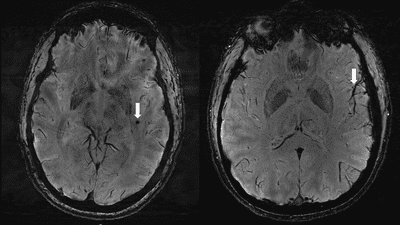

The study scanned 10 people with chronic migraine, 10 with episodic migraine without aura, and five controls who didn’t experience migraine to look for differences. As well as checking for changes in the perivascular spaces, they were looking for white matter hyperintensities: a type of lesion that’s seen in people who get migraines.

Scans revealed that there were significant changes in the perivascular spaces within the centrum semiovale in the participants who got migraine. For this group, the quantity of these changes was correlated to the presence of white matter lesions.

“Although we didn’t find any significant changes in the severity of white matter lesions in patients with and without migraine, these white matter lesions were significantly linked to the presence of enlarged perivascular spaces. This suggests that changes in perivascular spaces could lead to future development of more white matter lesions.”